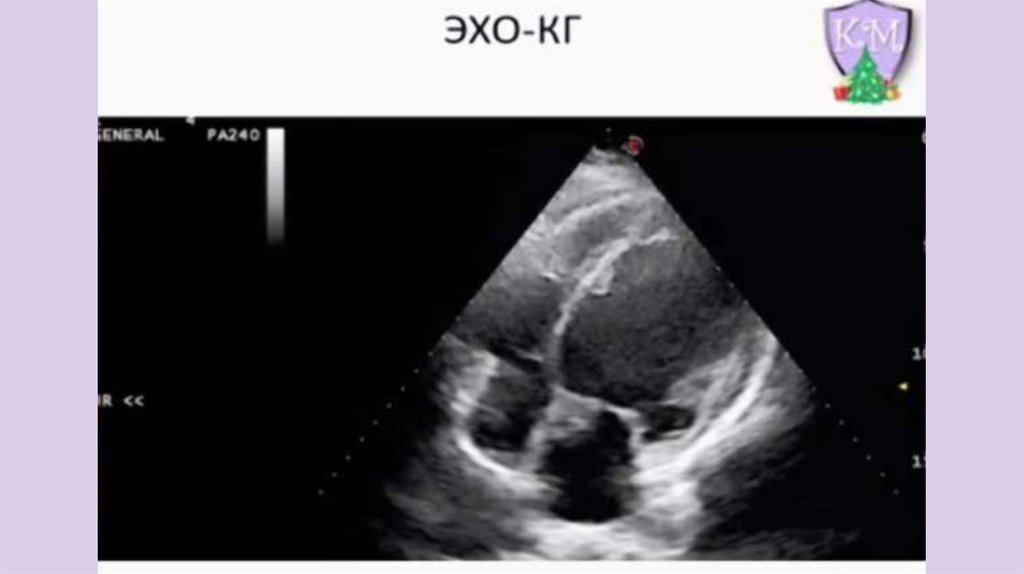

Пациентка М., 15 лет, с рождения быстро

утомляется при физических нагрузках, отмечает

эпизоды одышки с акроцианозом. Предположите

диагноз

13.

14.